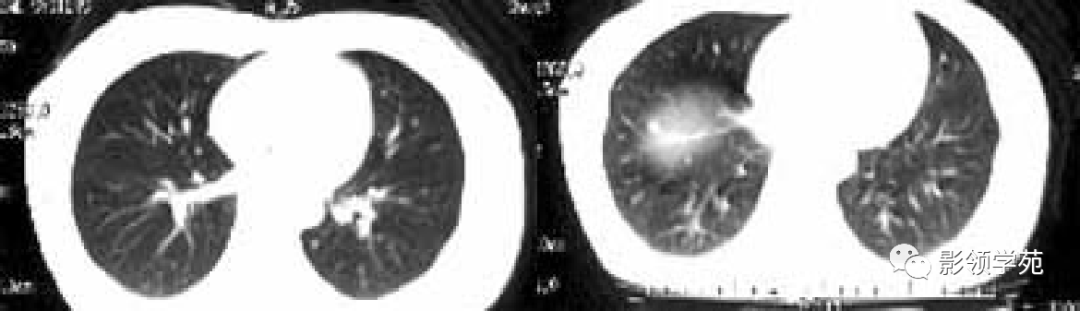

2.淋巴道转移:HRCT表现为沿淋巴管分布的结节。支气管血管束结节状增粗,并有结节,小叶间隔呈串珠状改变或增粗,小叶中心有结节灶,并有胸膜下结节。病变在两肺弥漫分布或局限于某一部位,以中下肺多见。常合并胸腔积液。约半数病人有纵隔及肺门淋巴结肿大。

患者阴道不规则流血半年,于是做宫颈检查发现宫颈糜烂,涂片发现癌细胞,而考虑肺转移瘤!